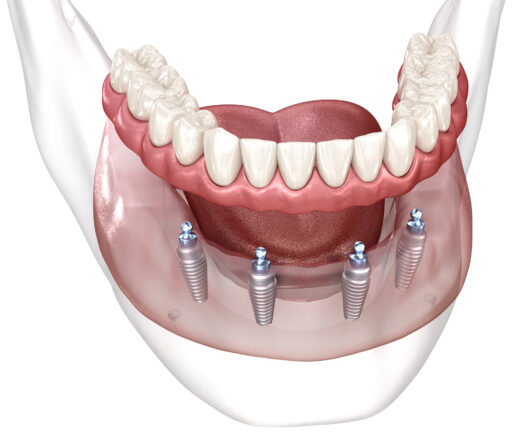

The Dr. Marco A. Muñoz Cavallini Dental Clinic has been a trusted name in dental care since 1968. Founded by renowned, certified prosthodontist and dental implant expert Dr. Marco Muñoz Cavallini, our clinic has grown to include Dr. Marco Muñoz Peralta, a distinguished dental implant specialist, along with an exceptional team of dental specialists, digital dentistry professionals, and restorative experts. With a remarkable track record of placing and restoring over 60,000 dental implants and more than 100,000 crowns and bridges since 1980—including over 10,000 All-on-X cases—we stand out as leaders in the field.

Our 57 years of collective experience, including 45 years dedicated to dental implants, positions us among the finest dental practices in Costa Rica. What sets us apart? Our comprehensive range of in-house dental services allows us to tailor our approach to your unique needs, whether it’s a transformative smile makeover, advanced restorative work, or aesthetic enhancements.